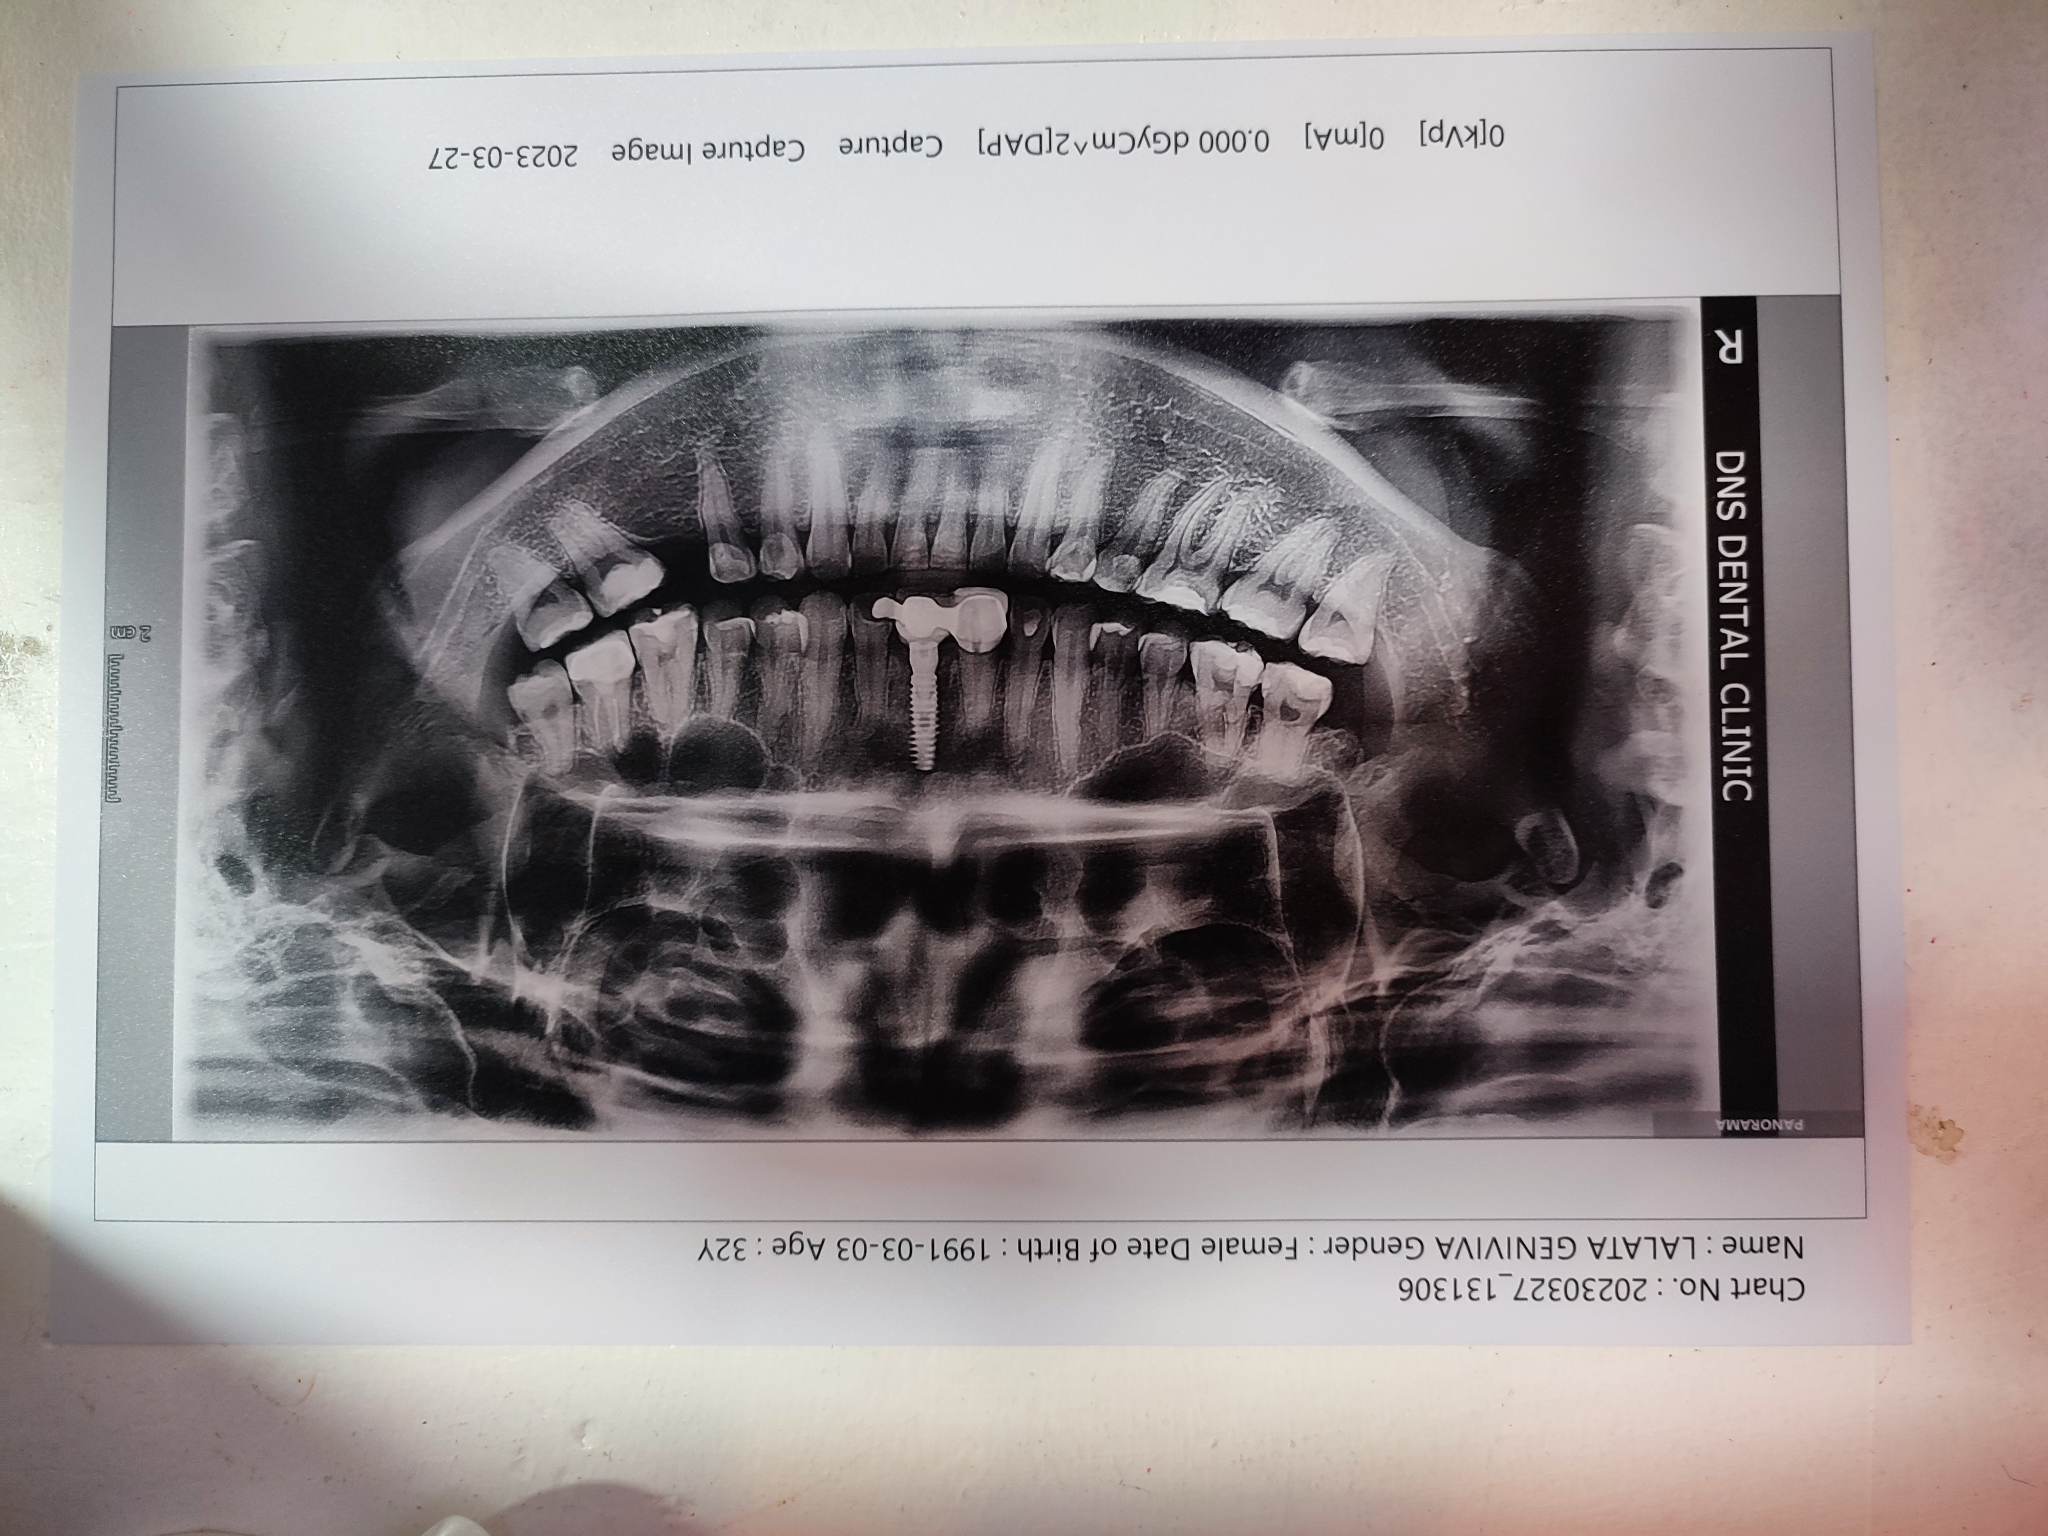

Edit Record Check our patient data records. Add patient information Patient Info Profile picture Last Name First Name Middle Name Birthdate Age Street Barangay City Country Zip Code Contact number Email Procedure 12-05-2019 > OP = 1,000 > LC # 34 = 800 > #35 = 1,500 01-17-2020 > TF #26 DISTAL = 500 > CAOH LINER = 400 > XRAY #26 PA = 800 01-25-2020 > #26 - OCCLUSAL DISTAL LINGUAL = 1,500 > CAOH 12/04/21- Op Lc- 47o/ 46 ob+caoh/ 44 ob/ 37 o+mta, b+mta *37-observe 14 O/ 12 lingual pit 04/19/22- inc and drainage 27 lingual 27 for RCT 5/28/22- 27 PFM shade A3 body/ b3 cervical 06/8/22- 27 PFM installed ( GC- GI) ff up after 1 wk. cervical lingual to observe -GTECh case 8/23/22- bone augmentation/ PRF+ CGF on tooth 21. next check up: after 7 days 03/20/23- Intentional bone graft 0.25 cc cancellous Bone BIO-OSS Poncho Technique ( 2mm healing abutment) PRC/ RCF 3,6 X 13 mm (IU implant) (mini) 1 stage technique Healing abutment 4.0x GH 2mm(mini) Full thickness MucoPeriosteal Flap Combination of Resorbable and non Resorbable suture. with OP 10/07/23- check up *** 10/18/23- 11/21 (abutment installed) - IU SB hex mini 4.0-3x7mm with analogue mini IU digital scanning done shade A3/B2 10/28/23- 11 zirconia crown installed/ 21 implant zirconia crown installed 05/11/24 OP air polisher Xray of implant 12/21/24 OP xray LC #25 Occ LC #45 Occ. Distal (deep) 03/29/25 LC #34 O 03/24/26 OP w/airpolisher flouride varnish File maam_lalata.jpg File 2 image_50461441.jpg File 3 File 4 File 5 File 6 File 7 File 8 File 9 File 10 File 11 File 12 File 13 File 14 File 15 File 16 File 17 File 18 File 19 File 20 Retain Record Retain Record Yes No Save Your Changes